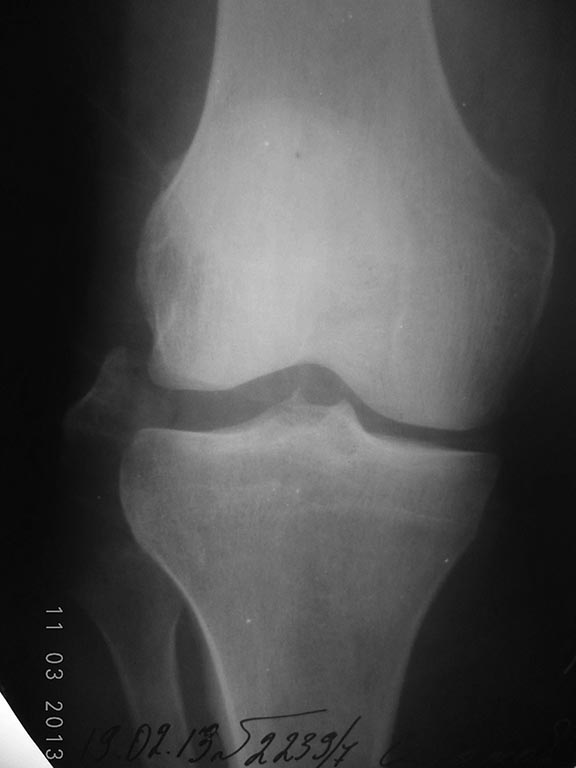

Авульсионные переломы, т.е. отрывные повреждения связок можно лечить, как переломы. Здесь повреждение латеральной связки коленного сустава и огромный фрагмент, который можно фиксировать шурупом 3.5 мм. Меньшие фрагменты фиксировать чрескостными швами.

Конечность в разгибании до 4х недель, затем наладить движение в суставе, но 2.5 мес. ортез для предупреждения чрезмерных варусных движении. Снимок датирован февралем, будут трудности сопоставить фрагмент на место, а фиксацию надо комбинировать “шуруп +костные швы”.

Совершенно согласен с Алексеем насчёт МРТ колена. Так сместить головку малоберцовой кости невозможно не порвав обе крестовидные связки. И даже на рентгенах видно расширение латеральной части сустава. Так что скорее всего придётся оперировать и крестовидные связки. А малоберцовую кость можно будет зафиксировать интрамеддулярным винтом после открытой репозиции. Насчёт крестовидных связок есть много мнений о том как и когда их оперировать.